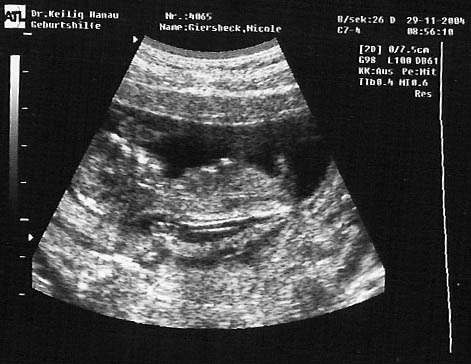

Meine Ultraschall-Bilder